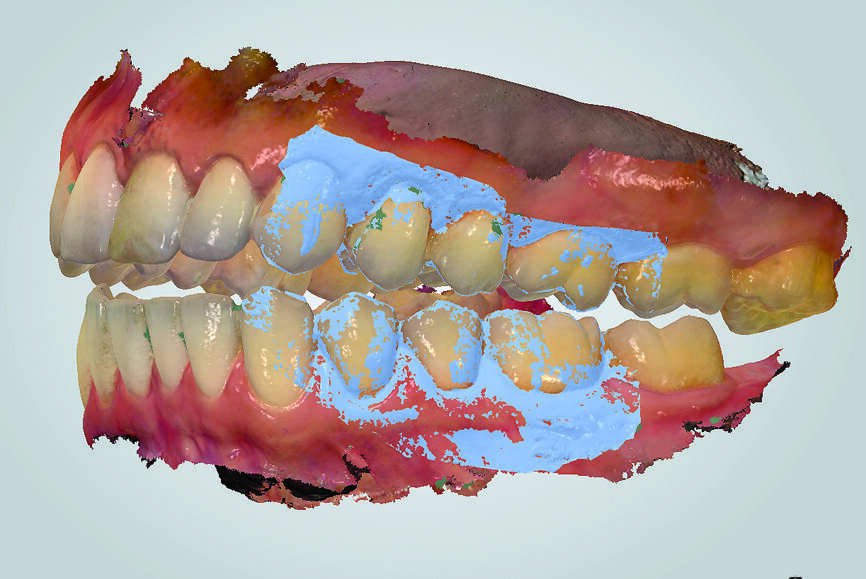

In contrast, digital recording has several advantages regarding efficiency and accuracy. The recording takes place without an interposed medium. The uploading of the digital casts in the software to the IC or CR position happens without the need for positioning of physical stone casts by an operator (technician). This ensures an accurate and efficient mounting in the virtual articulator. The direct digital occlusal recording is based on the intra-oral scanner software matching the digital casts of the arches to the inter-arch scan obtained from the side view of the arches (Fig. 18). The only noted disadvantage of the direct digital recording relates to the additional cost of acquiring an intra-oral scanner and the learning curve associated with operating one.

When the dentist decides to maintain the existing bite, that is, to work with what is there, the focus should be on ensuring that there is no unwanted change in the recording and transmission to the laboratory. Analogue recordings of existing IC can be performed using polyvinylsiloxane registration pastes or waxes (Fig. 19). Dental laboratories usually digitise the analogue records and fabricate the restorations digitally. The process of digitisation can introduce imprecisions, owing to the difficulty of the laboratory articulating the models in the precise position. Digital recordings of existing IC can be performed using intra-oral scanners. The scanner is placed in the buccal corridor and records the relative position of the maxillary and mandibular teeth (Figs. 20a & b).